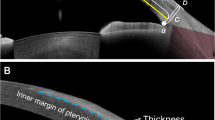

According to the complaint of the volunteers, the disposable capillary tear collector was used under the tear lamp to collect one drop of tear tears from the pterygium eye. The collected tears were dropped into the sample area of the LT-a test card (Guangdong Shengze Kanghua Biomedical Co., LTD.). The LT-a test reagent was dropped into the reagent area of the test card, and then the name of the volunteers and the sampling time were recorded on the LT-a test card and left for 10 min. Place the card analyzer and read the parameters (including qualitative results and LT-a concentration). Regardless of whether the antigen is present in the sample, the red nanosphere labeled antibody B is combined with antibody C located in the quality control region to form a red band to determine whether the chromatography process is expected (Fig. 1). The immunochromatography will show qualitative results and LT-a concentration at the end of testing.

LT-a reagent testing card. The detection card has three areas: the test area containing antibody A, the quality control area containing antibody C, and the sample area with tear drops, where antibody B labeled with red nanospheres, is present. During testing, the sample undergoes chromatographic effects.